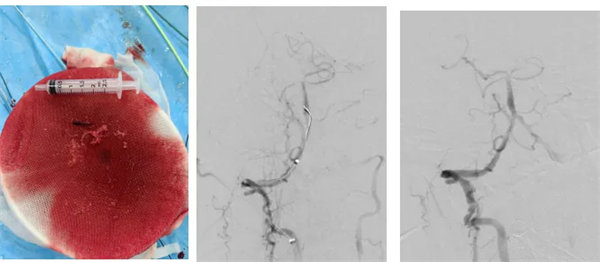

術(shù)中,介入團(tuán)隊(duì)精準(zhǔn)定位血管閉塞部位,通過(guò)微導(dǎo)絲“探路”聯(lián)合球囊擴(kuò)張技術(shù)開(kāi)通右側(cè)椎動(dòng)脈開(kāi)口,造影椎開(kāi)口殘余狹窄60%。基底動(dòng)脈血栓形成,基底動(dòng)脈管腔狹窄55%,基底動(dòng)脈尖堵塞,右側(cè)大腦后動(dòng)脈及小腦上動(dòng)脈未見(jiàn)顯影,左側(cè)大腦后動(dòng)脈P3以遠(yuǎn)閉塞。

席聰準(zhǔn)確鎖定患者基底動(dòng)脈處血栓,采用抽吸取栓技術(shù)快速開(kāi)通血管,成功取出堵塞部位2cm的血栓。再次造影示:右側(cè)大腦后及雙側(cè)小腦上動(dòng)脈再通,右側(cè)大腦后動(dòng)脈P3段以遠(yuǎn)閉塞,考慮慢性閉塞,推注替羅非班,血流明顯加快。隨后采用支架植入術(shù)開(kāi)通右側(cè)椎動(dòng)脈開(kāi)口處,術(shù)中影像顯示:支架貼壁良好,無(wú)明顯殘余狹窄,顱內(nèi)血管顯影良好。